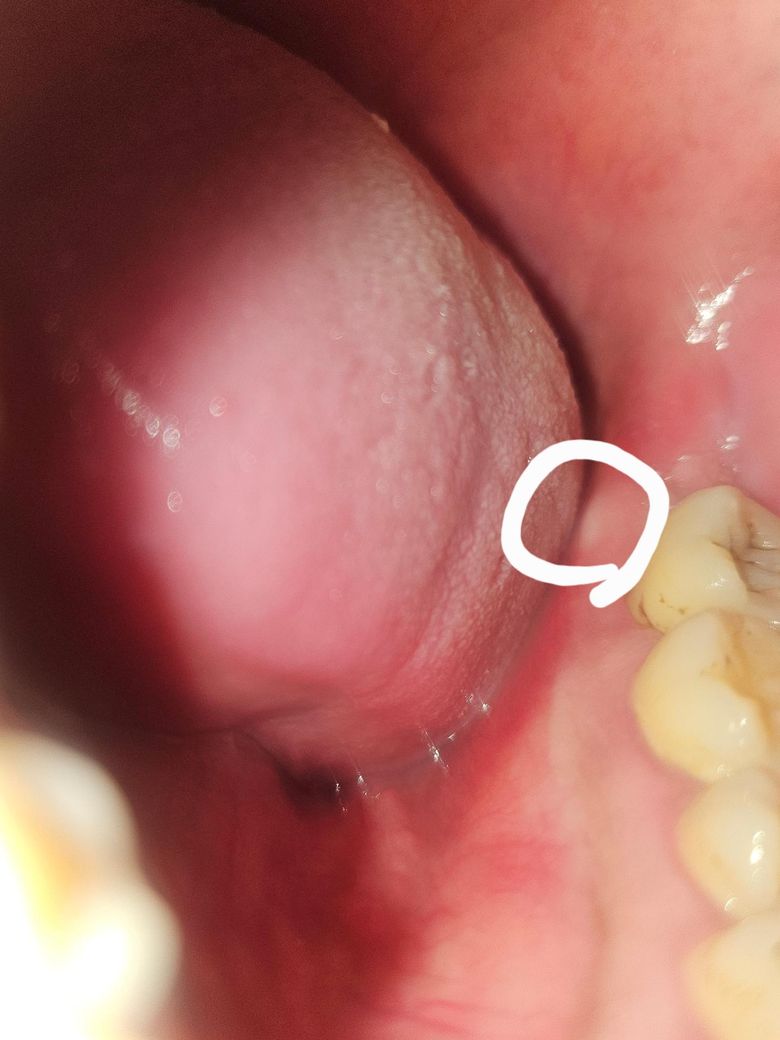

사진속 동그라미 처럼 잇몸에 고름이 있습니다.

그리고 그 근처 부위인 어금니가 흔들립니다.

통증또한 심해서 반대쪽으로만 씹고있어요

이만 다물어도 통증이 느껴집니다,

증상이 그렇다면 그 흔들리는 어금니에 염증이 생겨서 그게 치아 뿌리끝으로 나와 잇몸을 뚫고 나오려는 것입니다. 신경치료를 해서 나아질 수도 있지만 염증이 심하다면 발치를 해야할 수도 있습니다. 일단 치과에 가셔서 엑스레이를 찍어보고 진료보시는게 좋을 것 같습니다. 어차피 가만히 놔둬도 낫는게 아닌데 오래 방치하다가는 잇몸뼈도 더 많이 무너지고, 다른 치아에까지 피해가 가니까요.

잇몸 내지는 주변 치아에서 비롯된 염증으로 농양이 잡힌겁니다 원인이 뭔지에 따라 잇몸치료 내지는 신경치료로 치료방향이 달라집니다

치아의 통증과 흔들림, 주변부 잇몸의 부어오름과 고름으로 보아 급성 또는 만성 치주농양으로 추정할 수 있습니다.

이는 잇몸의 세균감염이 잇몸 조직 깊숙이 침투되었을 때 나타날 수 있습니다. 간혹 치주질환 없이도 발생하나 굉장히 드문 경우입니다.

따라서 빠른 시일 내에 치과에 내원하여 방사선 사진을 활용한 정밀 진단을 받고, 잇몸과 주위 구강 조직에 대한 치료 계획을 세울 필요가 있습니다.